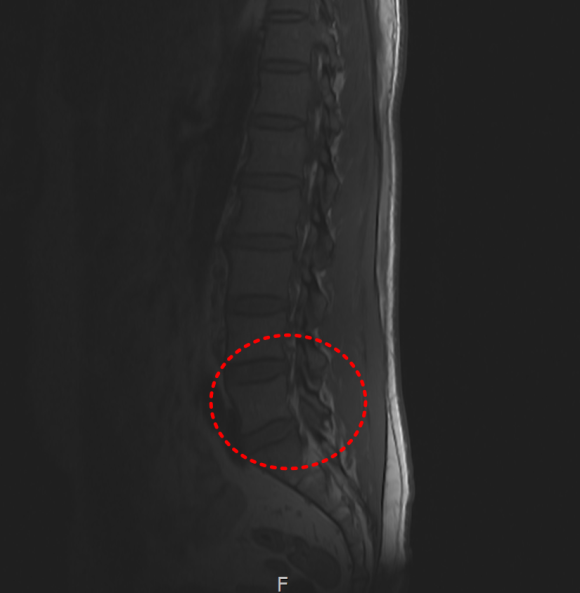

경추 X-ray

SLAP 파열 & 일자허리

일자목 & 디스크 팽륜